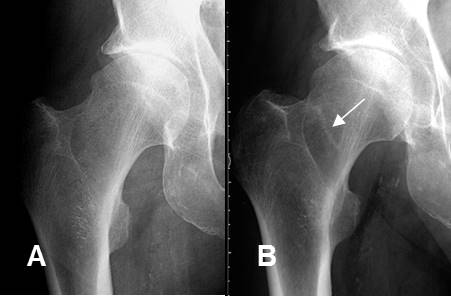

Fig 15. Derrame articular.

A: Rx AP. Desplazamiento lateral del cojinete graso glúteo, que hace sospechar derrame articular.

B: RM coronal y C: RM axial en STIR. Se confirma el derrame articular, por artritis infecciosa.